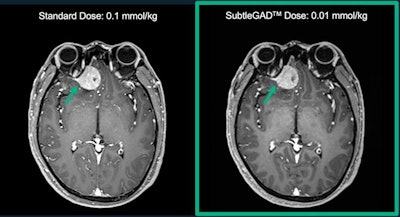

SubtleGAD uses AI to reduce necessary gadolinium dose during MR exams, and it can process images at 10% of typical doses, the company said. It is part of the company's portfolio of AI tools for radiology, which also includes SubtleMR and SubtlePET.